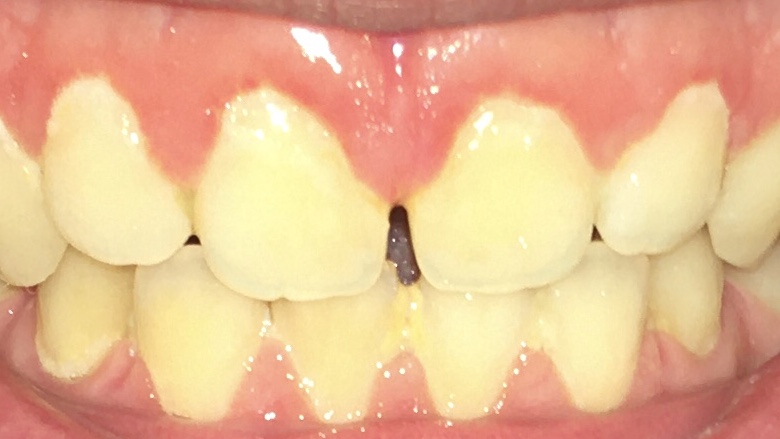

Опустились дёсны в нескольких местах, обнажились шейки зубов. Чувствительные, болят от прикосновений, могут реагировать на холодное, горячее, сладкое.

Ситуация как примерно на пик2.